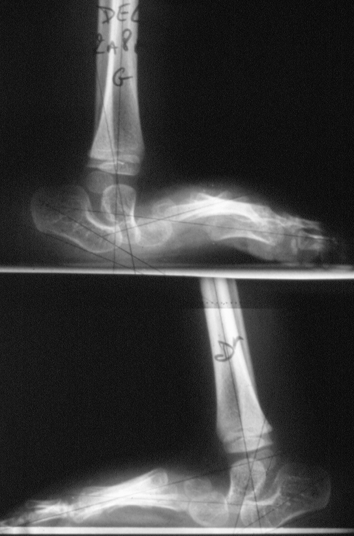

L’existence d’une luxation dorsale du milieu du pied (talo-naviculaire) avec équin de l’arrière pied explique l’aspect convexe global et le talon bossu.

L’hyper-mobilité en flexion dorsale de l’avant pied peut donner à tort une impression de réductibilité et par conséquent évoquer le diagnostic de pied calcaneus (dont le pronostic est fort différent) ; la radiographie ou l’échographie peuvent être utiles pour redresser le diagnostic.